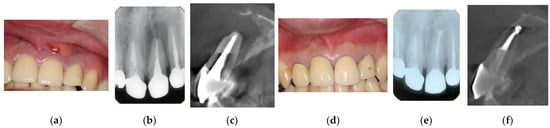

Figure 3. Clinical case 2. Female, age 35 yrs. (a) Intraoral view of the left maxillary incisor just before operation. (b) Preoperative periapical radiograph, with the “bone” defect presenting as a radiolucent area in both coronal and the middle of the root. (c) Flap retraction and debriding of the defect. (d) Photo of the extracted tooth, showing external root resorption (arrow).